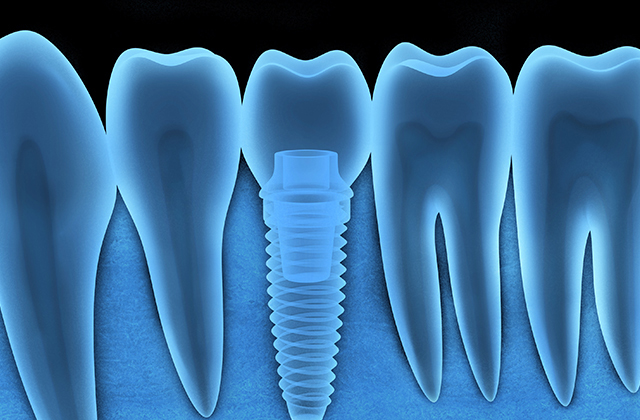

More InfoRoot Canal Therapy

Root Canal treatment can save a tooth from extraction and relieve pain caused by inflammation and infection